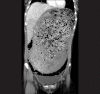

Acute gastric dilatation is a rare complication of anorexia nervosa binge/purge subtype that results from gastrointestinal abnormalities, including decreased gastric motility and delayed gastric emptying. Early diagnosis and intervention is critical since delay may result in gastric necrosis, perforation, shock, and death. We report a 26-year-old female with anorexia nervosa binge/purge subtype, who presented with abdominal pain and nausea after a binge episode. Abdominal radiography and computed tomography showed a grossly dilated stomach measuring 32 cm × 17.9 cm consistent with acute gastric dilatation. She underwent exploratory laparotomy with gastrotomy and gastric decompression, and recovered uneventfully. Initially, the patient denied the binge episode, as many patients with eating disorders do, but later revealed an extensive history of anorexia nervosa binge/purge subtype. This case stresses the importance of obtaining a thorough history of eating disorders and maintaining a high index of suspicion for acute gastric dilatation in young women who present with abdominal pain and distention.